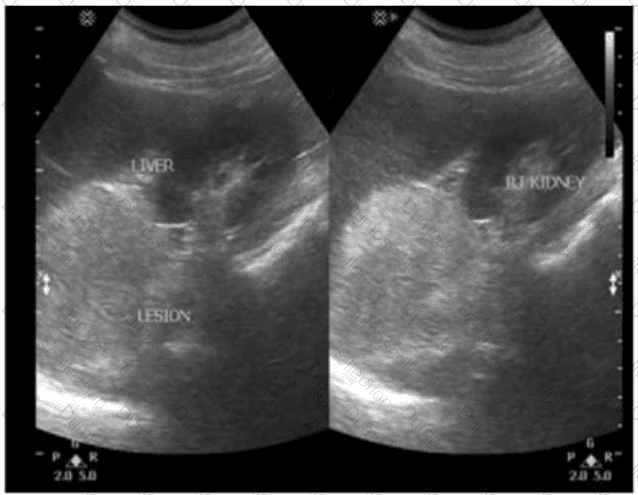

Which finding is most likely demonstrated in these images of a hypertensive patient with a history of hematuria?